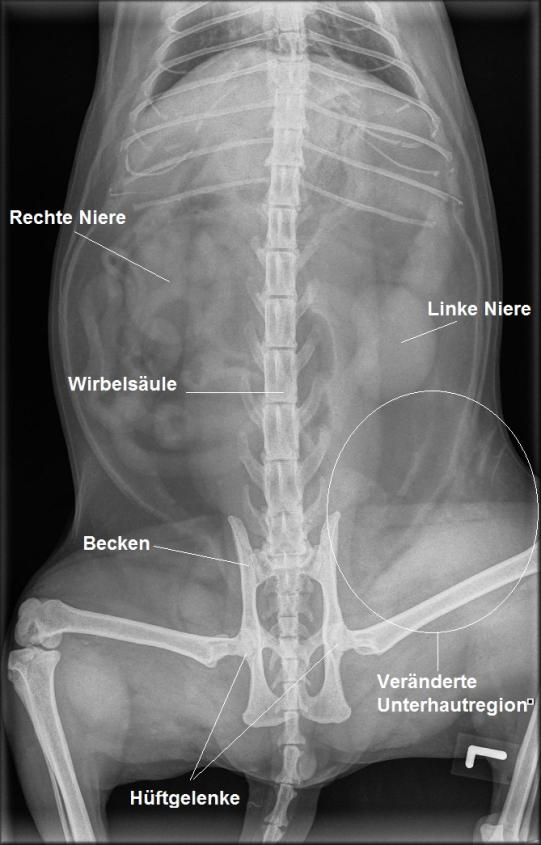

Obwohl Jimi bekannterweise ein ängstliches Tier ist, welches sich bei uns vor Schreck jeweils sehr zurückhaltend verhält, scheint er doch aussergewöhnlich ruhig. Die Körpertemperatur und der Allgemeinuntersuch sind unauffällig, jedoch ist in der linken Leistengegend das Unterhautgewebe diffus geschwollen, verhärtet und schmerzhaft. Die Haut selbst ist aber unversehrt. In einer Röntgenaufnahme ist erkennbar, dass die Knochen von Becken, Hüftgelenken und Oberschenkeln unversehrt sind; allerdings ist im Bereich der linken Leistenregion eine seltsame, streifige Röntgensignatur zu sehen, welche auf eine Flüssigkeitsansammlung im Unterhautgewebe hinweisen könnte. Ob sich Jimi hier einen Bluterguss zugezogen hat?